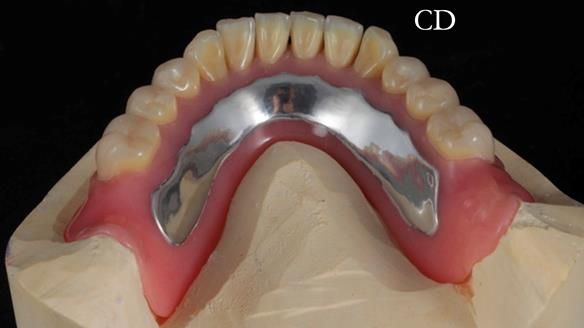

The detailed clinical situation and treatment process are outlined below, with clinical work provided by me and technical work by Rowan Garstang. The treatment spanned 12 months, involving removing 5 upper anterior teeth, adding to an existing upper RPD, followed by creating and fitting metal based complete dentures.